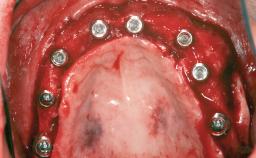

# of Implants 12

Type of Implants One-Piece|Reduced-Diameter

Bone Augmentation Horizontal|Staged

Augmentation Materials Autogenous chips|Autogenous block(s)|Membrane